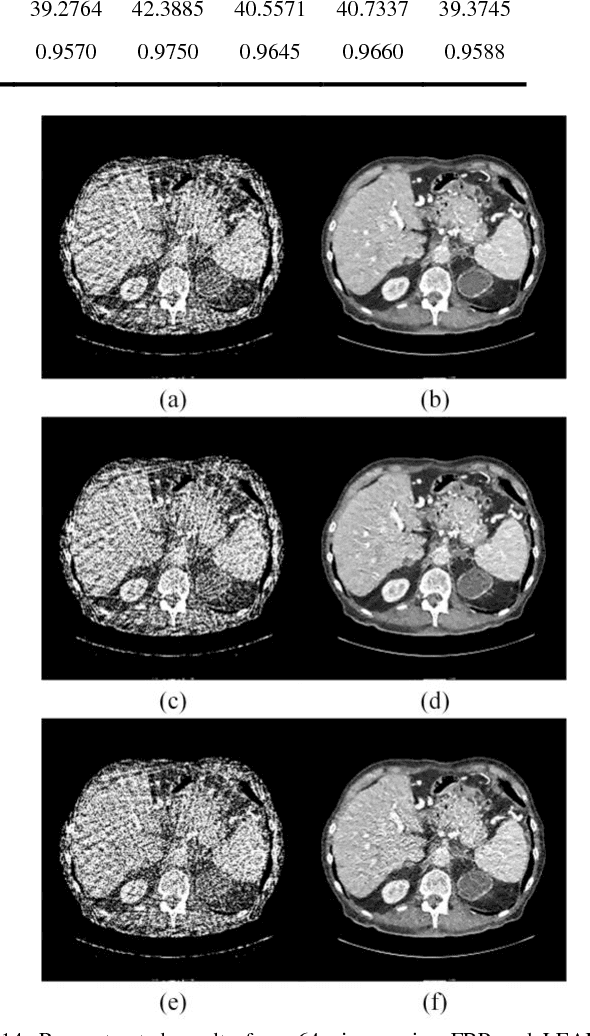

Abstract:Compressive sensing (CS) has proved effective for tomographic reconstruction from sparsely collected data or under-sampled measurements, which are practically important for few-view CT, tomosynthesis, interior tomography, and so on. To perform sparse-data CT, the iterative reconstruction commonly use regularizers in the CS framework. Currently, how to choose the parameters adaptively for regularization is a major open problem. In this paper, inspired by the idea of machine learning especially deep learning, we unfold a state-of-the-art "fields of experts" based iterative reconstruction scheme up to a number of iterations for data-driven training, construct a Learned Experts' Assessment-based Reconstruction Network ("LEARN") for sparse-data CT, and demonstrate the feasibility and merits of our LEARN network. The experimental results with our proposed LEARN network produces a competitive performance with the well-known Mayo Clinic Low-Dose Challenge Dataset relative to several state-of-the-art methods, in terms of artifact reduction, feature preservation, and computational speed. This is consistent to our insight that because all the regularization terms and parameters used in the iterative reconstruction are now learned from the training data, our LEARN network utilizes application-oriented knowledge more effectively and recovers underlying images more favorably than competing algorithms. Also, the number of layers in the LEARN network is only 12, reducing the computational complexity of typical iterative algorithms by orders of magnitude.